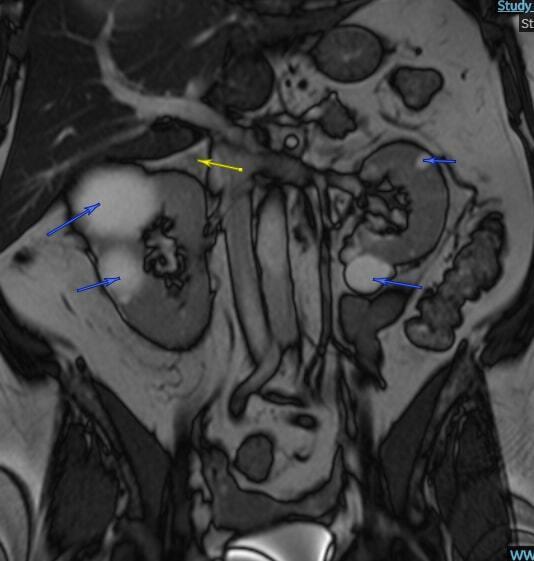

A case of phaeochromocytoma in a female patient in her 50s with phenotypical expressions for the rare Birt-Hogg-Dubé (BHD) syndrome is presented. Whether this is an incidental finding or that there is a composite relationship between these two entities remains to be fully described. Less than 10 cases reporting likely association of BHD syndrome with adrenal tumours have been reported in the literature to date.

本文报告了一例 50 多岁女性患者的嗜铬细胞瘤病例,该患者具有罕见的 Birt-Hogg-Dubé(BHD)综合征的表型表达。目前尚不清楚这是偶然发现还是这两种疾病之间存在复合关系。迄今为止,文献中仅报道了不到 10 例可能与 BHD 综合征相关的肾上腺肿瘤病例。